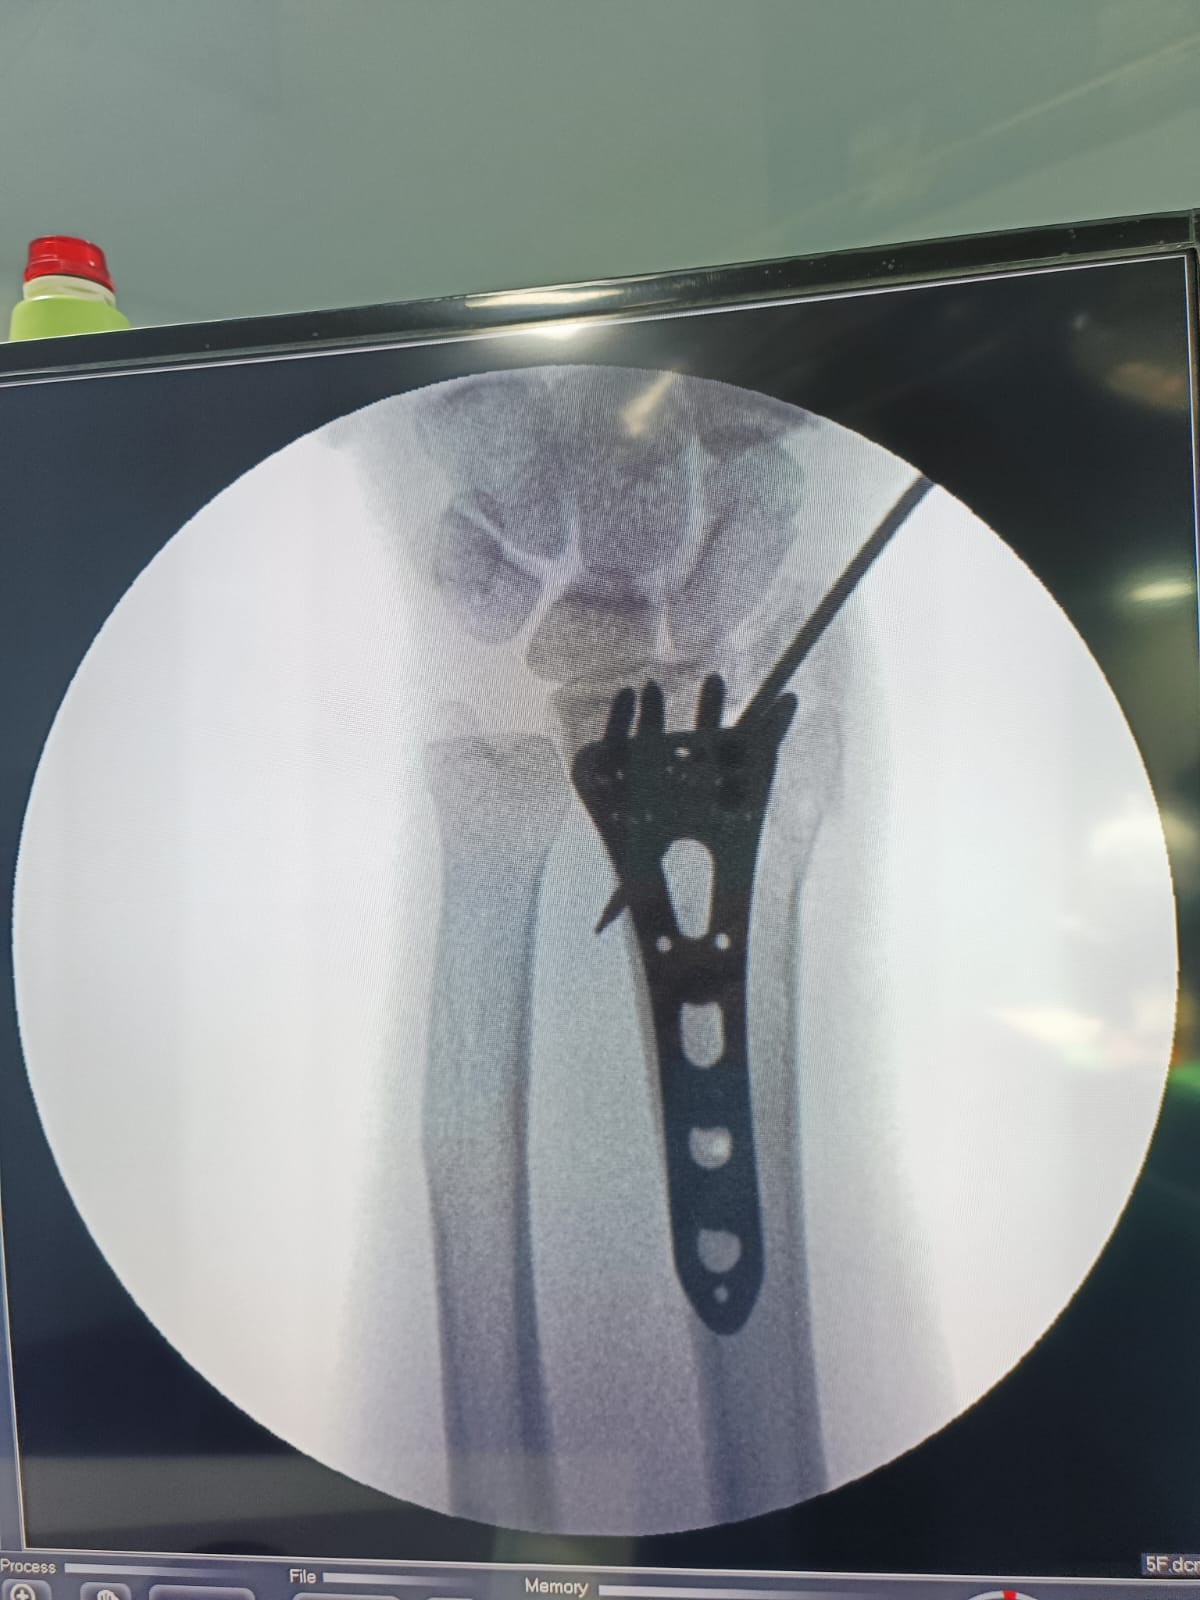

Fracture and Trauma Surgery

Gallery